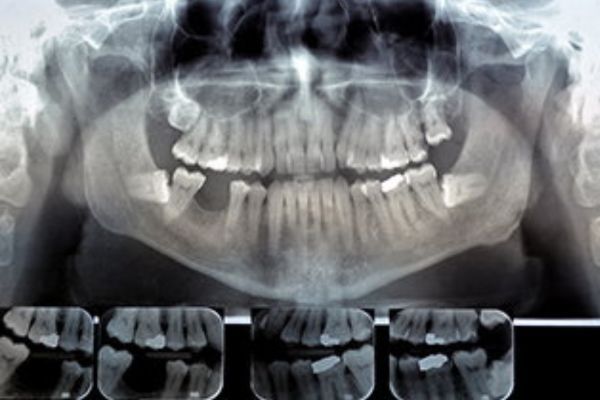

Cone Beam CT Imaging

Cone beam CT imaging provides dentists with a three-dimensional view of mouth, jaw, teeth, and nasal cavity. These images contain invaluable clinical information and help reduce the need for invasive procedures, shorten treatment time, and make treatment plans more effective and efficient.

With 3D scans, dentists and dental specialists can now evaluate:

Soft tissue size and location

This is especially important in diagnosing and treating sleep apnea, where soft tissue might be blocking the airways during sleep. These images will also show tumors and irregular growths, and can help your dentist plan for oral surgery.

Location of teeth, including impacted teeth or teeth that haven’t grown in yet

Knowing the exact location and size of your teeth helps in planning treatment for braces or impacted teeth.

Location, size and density of jaw bone

Knowing the location, size, density of your bones will help determine the best plan of action to take if you need an implant or jaw surgery.

When you get a cone beam CT scan, an imaging device rotates around your head. The scanner records between 150 and 600 different X-ray views in under a minute and sends the scans to a computer where a virtual, three-dimensional model is created from the images. The model can be rotated from side to side or up and down, magnified, or viewed from any angle needed. So not only can your dentist see your entire tooth’s anatomy, they can zoom in to see the condition of your root canal itself. This allows your dentist or dental specialist to prepare your procedure, or examine your health in great detail without you having to sit in an uncomfortable position, or without you even needing to be present.

Like X-rays, CT scans are associated with low amounts of radiation exposure, so it’s important to consider the risk before getting a scan. Most often, the benefits of getting a CT scan outweigh the risks, but it’s particularly important to be cautious for those with preexisting health conditions.

Digital X-Rays

X-rays are one of the most important parts of a dental exam, and can help medical professionals detect problems long before they are visible to the naked eye, including early tooth decay, gum disease, abscesses, and abnormal growths.

Benefits of Digital X-rays

Easy to obtain

Digital X-rays are obtained by putting a small electronic sensor in the mouth, and captured images can be pulled up instantly on a computer screen.

No waiting time

Unlike traditional X-rays that require an intermediary chemical process, your dentist can abstain and evaluate your X-rays almost instantly.

Images are clearer

Digital X-ray images are clearer than traditional X-rays and your healthcare provider can zoom in and out, making it easier for them to detect potential problems.

Easy to share and store

Digital X-rays can be easily emailed to different specialists if needed, and can easily be stored on your computer.

They are safer

Compared to traditional X-rays, digital X-rays reduce your exposure to radiation by up to 90%. Even though risk is reduced, there is still a slight risk that radiation from X-rays will cause cellular changes that may lead to future disease. Their benefits outweigh their risk, which is why they are so commonly used. Talk to your healthcare provider if you have questions about your safety, or why an X-ray is recommended for you.